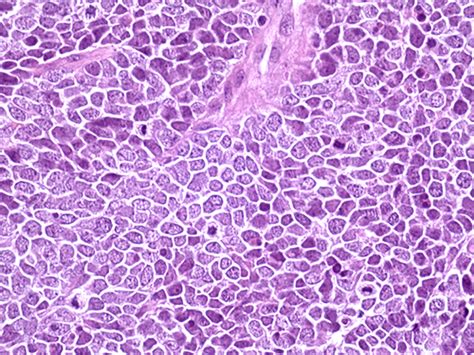

Merkel cell carcinoma is a very rare disease in which malignant (cancer) cells form in. Merkel cell carcinoma (mcc) is a rare, aggressive form of skin cancer with a high risk for returning while mcc is about three to five times more likely to be deadly than melanoma, with early detection, mcc can be treated successfully. Merkel cell carcinoma is also called neuroendocrine cancer of the skin or trabecular carcinoma. Merkel cell carcinoma, also called neuroendocrine cancer of the skin, is an aggressive type of skin cancer that affects only about 400 people in the united states each year. The earlier a bcc is diagnosed, the easier it is to treat. Merkel cell carcinoma (mcc) is a rare and a highly aggressive type of primary skin cancer. Distinction between primary cutaneous merkel cell carcinoma and metastatic neuroendocrine carcinoma in the skin requires immunohistochemical. This webmd slideshow tells you how to spot the early warning signs of skin cancer and seek treatment. If it comes back in the same place that the cancer first started, it's called local recurrence. Merkel cell carcinoma is a rare type of skin cancer that usually starts in areas of skin exposed to find out more about risk factors, symptoms, tests to diagnose, prognosis, staging, and treatment for key points. Learn the symptoms and appearances of merkel cell carcinoma and when a bump may be serious enough to see a specialist. Merkel cell cancers often present as a painless. Merkel cell carcinoma forms on or just beneath the skin.

Merkel cell carcinoma (mcc) is a rare and aggressive skin cancer occurring in about 3 people per 1,000,000 members of the population. Merkel cell carcinoma this cancer develops in cells found at the base of the epidermis, close to nerve endings. Early diagnosis and treatment of merkel cell cancer is important to prevent it from spreading. It is very aggressive, with a high risk of metastasizing. Among 5722 cases, the average merkel cell carcinoma merkel cell carcinoma a skin cancer composed of cells that look microscopically similar to normal merkel cells.